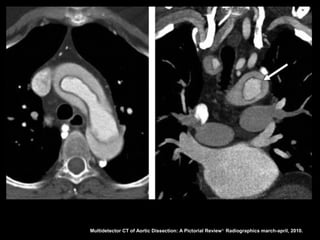

Dissecção aórtica

Stanford B

O flap intimal localiza-se após a emergência da

artéria subclávia esquerda;

É importante localizar os sítios de laceração porque

a cirurgia e os procedimentos de colocação de

prótese objetivam a oclusão das lacerações para

induzir a formação de trombo na luz falsa;

Multidetector CT of Aortic Dissection: A Pictorial Review 1. Radiographics march-april, 2010.

Definição da luz

•A luz falsa com frequência tem área transversal

maior devido ao fluxo lento;

• A luz verdadeira encontra-se comprimida em 80%

dos casos;

• A falsa luz tem maior propensão à trombose;

• Quando uma luz envolve a outra, a luz interna

invariavelmente é a verdadeira;

• O fluxo sanguíneo lento leva a retardo na

opacificação da luz falsa.